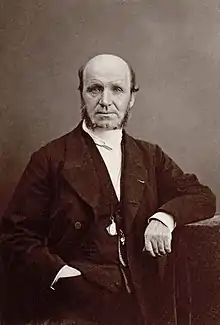

The disease was first described by the Neapolitan physician Giovanni Semmola in 1834 and Gaetano Conte in 1836.[42][43][44] However, DMD is named after the French neurologist Guillaume-Benjamin-Amand Duchenne (1806–1875), who in the 1861 edition of his book Paraplegie hypertrophique de l'enfance de cause cerebrale, described and detailed the case of a boy who had this condition. A year later, he presented photos of his patient in his Album de photographies pathologiques. In 1868, he gave an account of 13 other affected children. Duchenne was the first to do a biopsy to obtain tissue from a living patient for microscopic examination.[45][46]